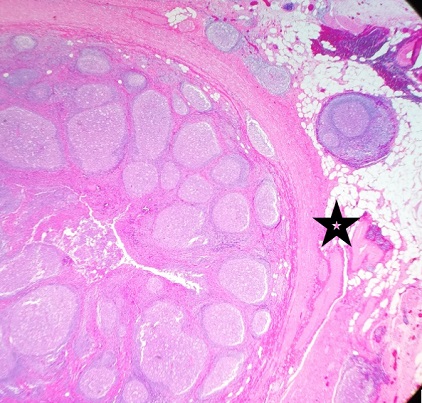

En el estudio de anatomía patológica se observó un apéndice ileocecal de pared engrosada, con áreas de aspecto fibrinoide en la superficie y contenido fecaloideo en su luz. El engrosamiento mural de la pared descrito macroscópicamente se correspondía histológicamente con una marcada hiperplasia folicular linfoide en la submucosa, que se extendía a la capa muscular y la subserosa, sin signos morfológicos ni inmunohistoquímicos de malignidad. La mucosa mostraba áreas de erosión, con inflamación crónica transmural, sin granulomas sugerentes de enfermedad inflamatoria intestinal (Figs. 1 y 2). Desde que se realizó la apendicectomía, el paciente ha permanecido completamente asintomático y con exploración física normal en las revisiones realizadas en consulta.

| Figura 2. Anatomía patológica de apéndice cecal. Imagen histológica (10×, tinción hematoxilina-eosina) de la mucosa, pared y tejido adiposo subseroso, del apéndice, con presencia en todas ellas de folículos linfoides reactivos con centros germinales de morfología heterogénea |